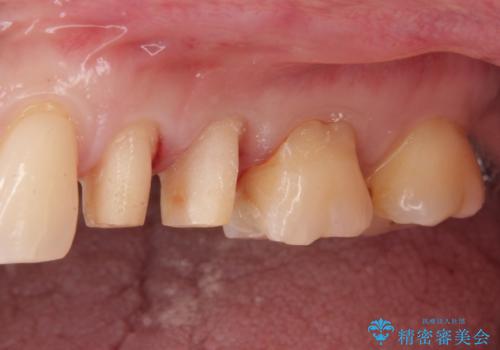

- 銀歯を白くしたい。水が少し染みるとの事で来院。

歯と歯茎の境目にプラスチック樹脂の治療の後があり、そこが染みる原因となっていました。

拡大鏡下で銀の詰め物、古いプラスチックの樹脂を外し、虫歯が残ってないかを確認して

ジルコニアクラウンで治療を行いました。